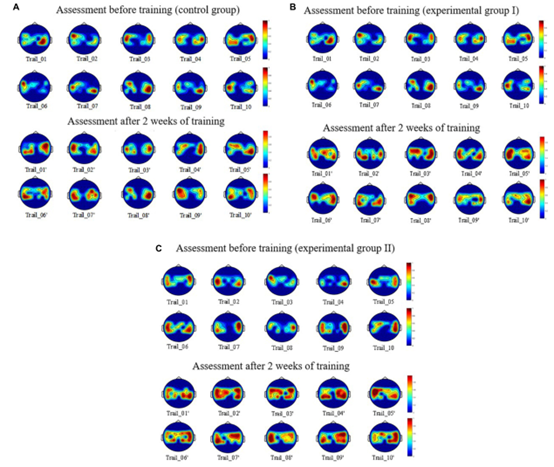

图7 三组场景下的训练MI任务前一天和训练MI任务14天后的BEAM比较

图7显示了受试者大脑区域神经激活的空间分布:S1(A. Control group)、S4(B. Group Ⅰ)和S8(C. Group Ⅱ),在增强MI任务训练的前后比较。图7A显示,受试者接受本研究设计的康复策略训练后,大脑区域运动神经的激活范围显著扩大(即MI神经的激活宽度增加)。图7B显示,受试者接受康复策略训练后,激活区域的颜色更暗(即ERD/ERS现象更明显),这表明MI神经的激活深度增加。图7C显示,与静态场景和动态场景相比,该策略对VR场景中MI神经的激活广度和深度有更明显的影响。